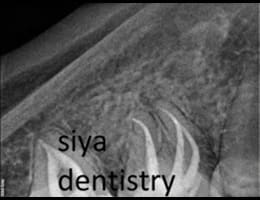

The dentist examines the tooth and takes X-rays to confirm the extent of infection or damage.

The infected or damaged pulp is removed using specialized instruments. The root canals are then cleaned and shaped to ensure they are free of bacteria and debris.

DIGITAL X RAY “RVG”

We invest in the latest imaging technologies like Carestream RVG IOPA to provide superior diagnostic capabilities.

Our experienced dental team is skilled in interpreting RVG IOPA images, ensuring that any dental issues are accurately identified and addressed.